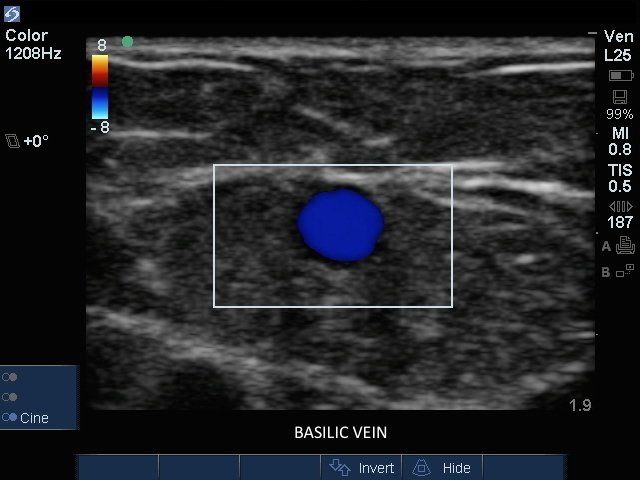

贵要静脉横切面图像